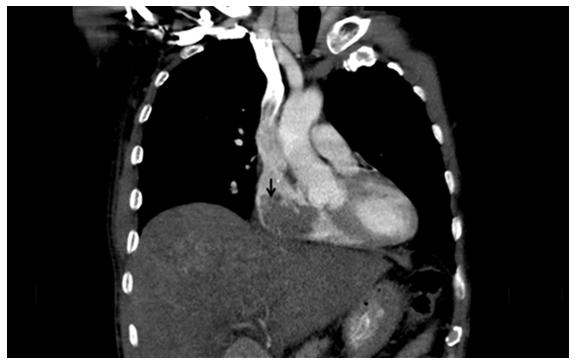

Computed tomography scan showing a mass extending into the right atrium. (Page 255)